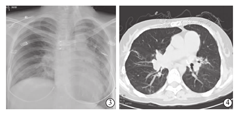

随访至术后147 d,受者心、肺功能恢复良好,术后98 d时胸部X线片显示:右下肺野及左侧肺纹理增粗、模糊,两肺门影尚清晰,心影稍增大,肺动脉段稍突起,双膈面及双肋膈角清晰(图3)。术后113 d胸部CT检查显示:双下肺炎症(右下肺为主),心脏增大,肺动脉高压(主干横径达35 mm),纵隔及肺门淋巴结钙化(图4)。肺功能检查显示:极重度限制性通气功能障碍,FVC占预计值32.2%,FEV1占预计值26.8%,FEV1/FVC 86.4%。生活质量得到明显改善,6分钟步行试验明显改善(由术前250 m提高至560 m),步行试验后Borg呼吸困难评分为2分;纤维支气管镜检查显示:双侧支气管炎症表现,黏膜轻度水肿,少量黄白色膜状物覆盖,左侧支气管吻合口稍微狭窄。